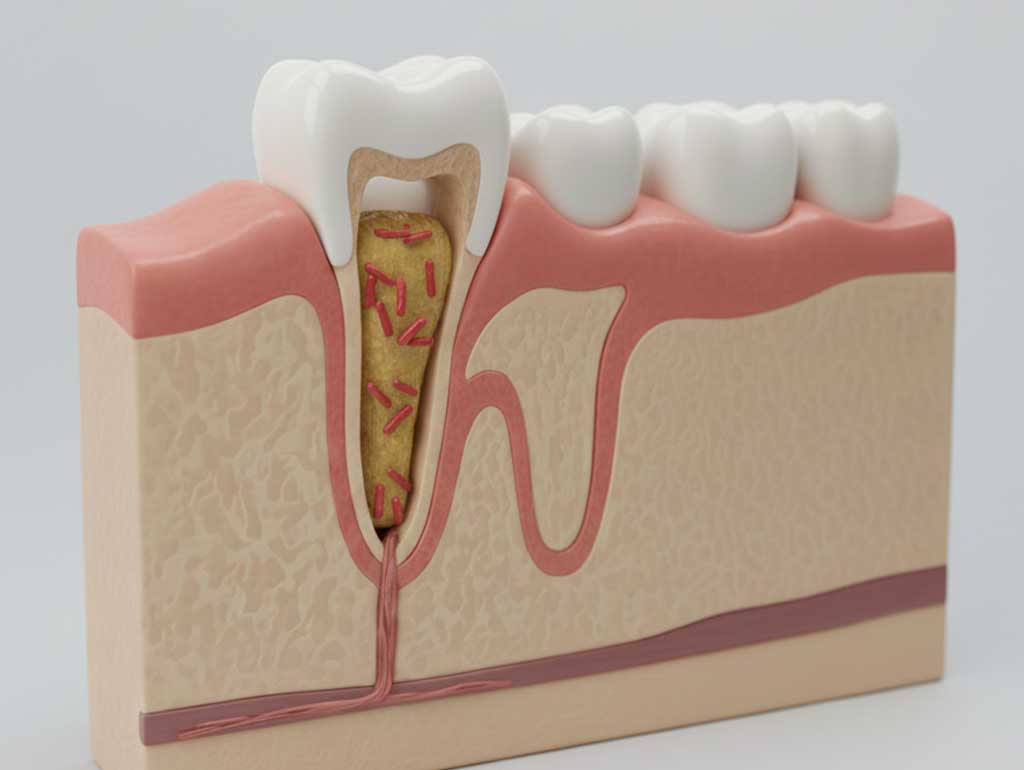

Die Hauptursache für die Parodontitis ist der Zahnbelag. Dieser Belag besteht aus Bakterien, die über, aber vor allem auch unter dem Zahnfleisch liegen. Die Bakterien des Zahnbelages produzieren unterschiedlichste schädliche Stoffe, die zu einer Entzündung des Zahnfleisches führen. So schwillt das Zahnfleisch an, beginnt zu bluten und es bilden sich Zahnfleischtaschen. Falls in diesem Stadium keine Behandlung durchgeführt wird - Aufklärung des Patienten über die richtige Pflege sowie Entfernung des Zahnbelages, Politur der Zähne und Optimierung der Zahnpflege - so ist eine weitere Vermehrung der Bakterien des Zahnbelages in den Zahnfleischtaschen nicht zu verhindern.

Der allgemein übliche Begriff Parodontose wird meist im falschen Zusammenhang gebraucht. Verbreiteter ist die Parodontitis – die entzündliche Form der Kiefererkrankung. Dabei spielen bakterielle Beläge die Hauptrolle. Auch die mangelnde eigene Abwehr des Organismus und andere begünstigende Faktoren wie z.B. ein veränderter Hormonhaushalt sollten nicht unterschätzt werden. Besonders gefährdet sind Raucher, da bei diesen die Blutzirkulation der Mundschleimhaut beeinträchtigt ist. Die grundlegende Problematik ist jedoch meist ungenügende oder mangelhafte Zahnpflege.